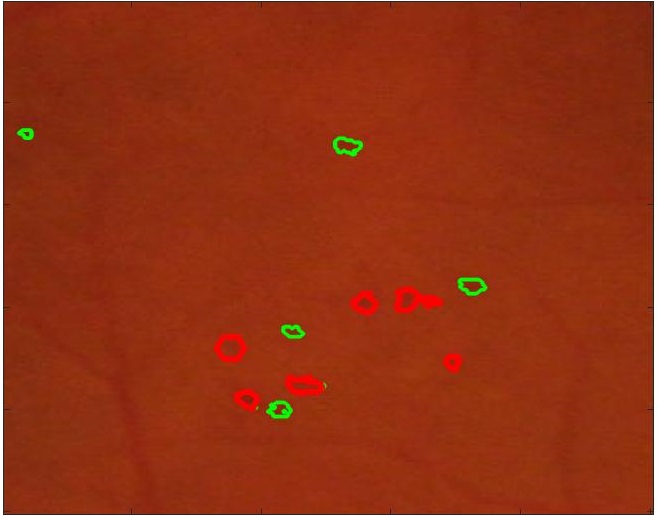

Figure 5 shows results of MA segmentation using the images generated by different super resolution methods. Figure 5 (a) shows the original full sized image with the regions having majority of the MAs outlined by a red square. Figure 5 (b) shows the cropped image region with yellow arrows identifying location of MAs. Figure 5 (c) shows manually drawn contours around the MAs. Figure 5 (d) shows the segmentation results obtained using the original HR images as part of the training and test set. The ground truth manual contours are shown in green while the segmentations obtained using the U-Net algorithm is shown in red. The performance on the HR images is an indication of the minimum error (or best possible segmentation performance). Figures 5 (e)-(h) show, respectively, the super resolved images obtained by , , and along with the super imposed segmentation results. It is quite obvious that the results obtained using are the best. It is interesting to note that the SR images obtained using and lead to blurred edges of the blood vessels and MAs, although in the case of the SR images are not blurred. The other two methods, and result in such poor quality images that the MAs are not even detected for this particular example.

![]() |

| (a) | (b) | (c) | (d) |

| (e) | (f) | (g) | (h) |